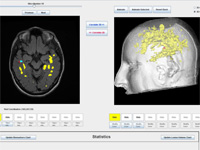

Integrative Visualization of Temporally Varying Medical Image Patterns

We present software for the visualization of temporal changes of disease patterns using stacks of medical images collected in time-series experiments. With this software users can generate 3D surface models representing disease patterns and observe changes over time in size, shape, and location of clinically significant image patterns. Statistical measurements of the volume of the observed disease patterns can also be obtained simultaneously.

(journal article, online article @JIB, reference).

A Novel MRI Visualization Tool for White Matter Pathology in Multiple Sclerosis

We developed a tool to visualize MS lesions and their 3D surface models to show changes in the lesions over time. These can be shown as an animation to elucidate differences across scanning sessions. With this software, a volumetric sub-region can be selected from the 3D model for zooming or animation, and a point on the 3D model can be selected to highlight all lesions connected to it. The total volume of lesions can be calculated, displayed as a chart, and exported.

(poster, online abstract @ SfN, reference).